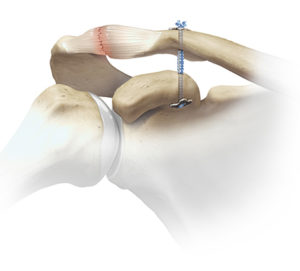

Die Schultereckgelenksverletzung ist eine der häufigsten Verletzungen bei Stürzen direkt auf die Schulter oder im Kontaktsport. Das betroffene Gelenk verbindet das Schlüsselbein mit einem knöchernen Fortsatz des Schulterblattes. Dieses ist durch mehrere Bänder sowie eine Kapsel gesichert. Je nachdem wie viele und welche Bänder verletzt sind entsteht eine Instabilität. Die Schmerzen sind am Anfang deutlich einschränkend.

Operative Therapie

Sollte eine massive Instabilität im Schultereckgelenk entstehen kann eine operative Stabilisierung nötig werden. Hier wird mit einem speziellen Flaschenzugsystem das Gelenk wieder in die Ausgangsstellung gebracht. Der Eingriff erfolgt mit kleinen Schnitten um das Weichteilgewebe möglichst zu schonen.

Nachbehandlung

Nach der OP erfolgt nach kurzfristiger Ruhigstellung in einer Schulterbandage die mobilisierende Therapie. Hier muss darauf geachtet werden die Beweglichkeit im Schultergelenk möglichst schnell wiederherzustellen. Für 6 Wochen besteht eine Sportkarenz.